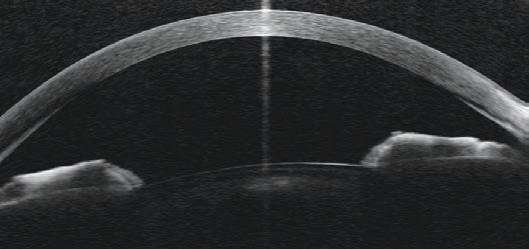

Objective measurements of OSD are obtained through clinical examination and various newer technologies. Factors that should be assessed include eyelid position, tear meniscus, tear film quality, tear quantity (Schirmer’s test), tear film break-up time (TBUT; less than 10 seconds being abnormal), meibomian gland dysfunction and any ocular surface staining with fluorescein.

Clinical examination can be augmented by several new technologies such as tear osmolarity testers and ocular surface analysers which measure lipid layer thickness (LLT), capture blink dynamics, and image meibomian gland structures. These technologies can be helpful in diagnosing OSD and monitoring progression. 8 They can also be used to perform baseline tests before initiating topical glaucoma therapy.